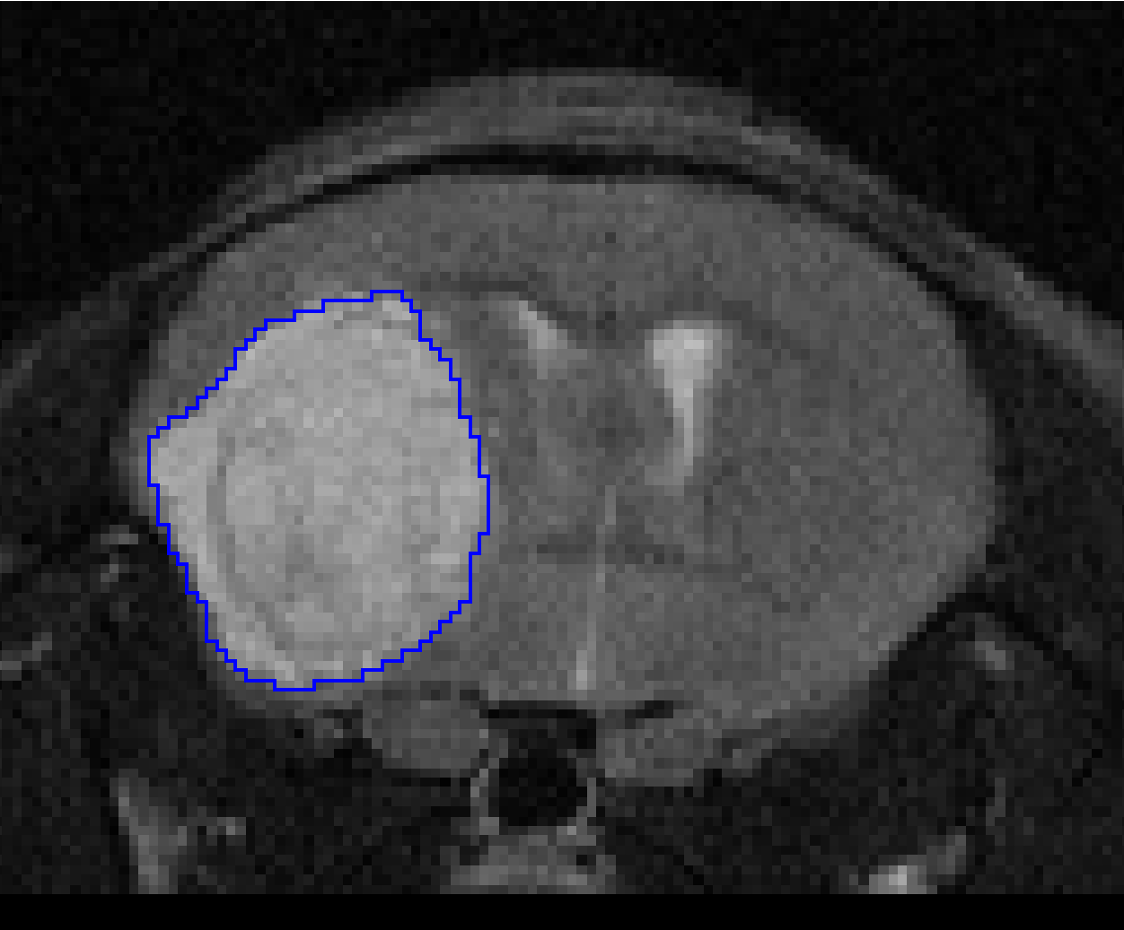

• Multimodality segmentation tools – comprehensive semi-automated and manual tools for precision and reproducibility